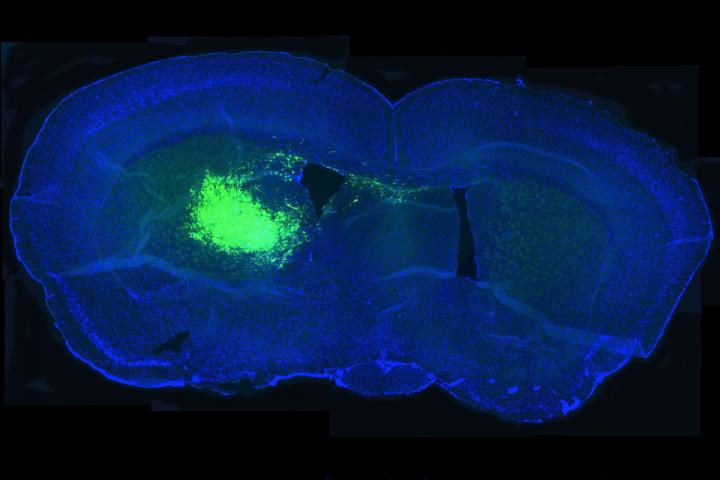

Scientists have identified a gene that is overactive in a deadly form of brain cancer known as glioblastoma, according to a study at Washington University School of Medicine in St. Louis. The findings suggest that inhibiting that gene may improve the outlook for glioblastoma patients.

The new research showed that glioblastoma patients with high expression of a gene known as NAMPT died sooner. Tumors with elevated expression of the same gene grew rapidly when they were implanted in mice and shrank when NAMPT was inhibited.

Using human glioblastoma cells, Albert H. Kim, MD, PhD, an assistant professor of neurological surgery, postdoctoral researcher Amit Gujar, PhD, and colleagues showed that NAMPT helped cancerous stem cells survive and proliferate, fueling the growth of existing tumors, while inhibiting NAMPT reduced the ability of the cancer stem cells to renew themselves.